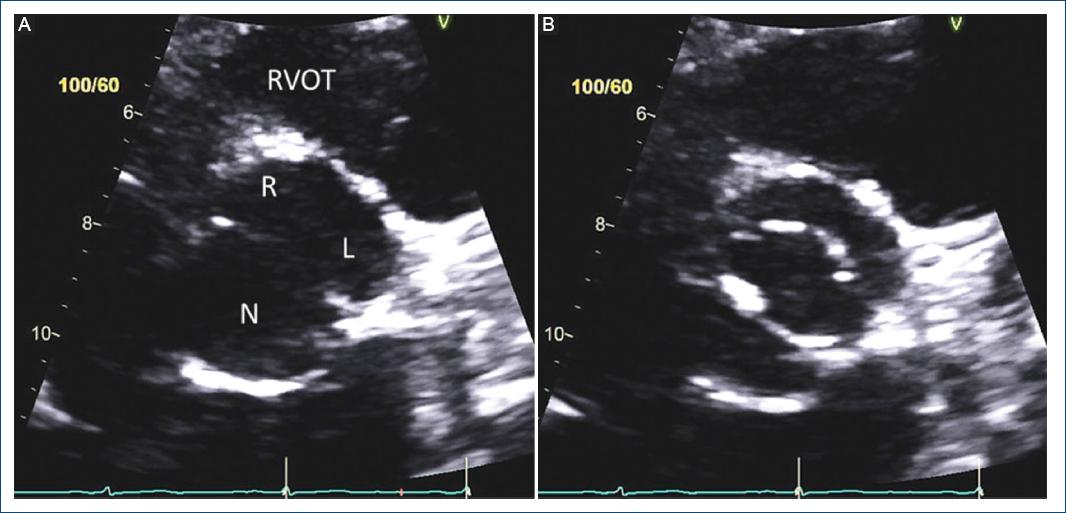

Figura 7 Imágenes de ecocardiografía transtorácica diastólica y sistólica de eje corto paraesternal de los tres fenotipos de la válvula aórtica bicúspide (VAB) fusionada. Aplicable a vistas tomográficas similares obtenidas con tomografía computarizada cardiaca y resonancia magnética cardiaca. A: VAB de tres senos aórticos distinguibles con fusión de cúspide derecha-izquierda, con rafé (flecha) en diástole y B: apertura sistólica típica con comisuras marcadas como la esfera del reloj (flechas). C: VAB de tres senos aórticos distinguibles con fusión derecha-no coronaria, con rafé (flecha) en diástole y D: apertura sistólica típica con comisuras marcadas como la esfera del reloj (flechas). E: VAB de tres senos aórticos distinguibles con fusión izquierda-no coronaria, con rafé (flecha) en diástole y F: apertura sistólica típica con comisuras marcadas como la esfera del reloj (flechas) (modificada de Michelena et al., 201811 con permiso de Elsevier). R: cúspide coronaria derecha; L: cúspide coronaria izquierda; N: cúspide no coronaria.

Figura 8 Tipo fusionado con fusión de cúspide derecha-izquierda sin rafé visible y ángulo comisural simétrico. A: imagen diastólica de eje corto de la ecocardiografía transtorácica que muestra la fusión de la cúspide derecha-izquierda sin rafé visible (poco frecuente) y ángulo de 180° de las comisuras de la cúspide no fusionada, sin embargo los tamaños y formas de las dos cúspides funcionales son diferentes, la cúspide unida es más pequeña que la cúspide no coronaria (N) no fusionada y existen tres senos aórticos. B: imagen sistólica de ecocardiografía transtorácica de eje corto que confirma la ausencia de un rafé visible y el ángulo comisural de 180°. R: cúspide coronaria derecha; L: cúspide coronaria izquierda; RVOT: tracto de salida del ventrículo derecho.